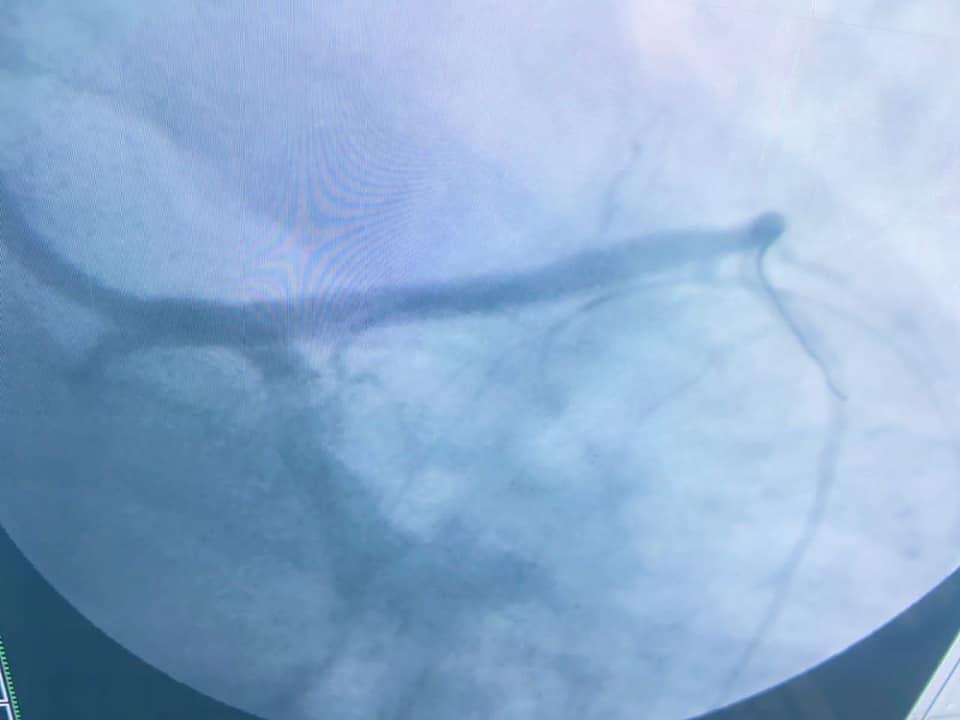

من ناحيته، أوضح الدكتور شرف الدين شاذلي، رئيس وحدة قسطرة القلب بالمستشفى الجامعي، أن فريق العمل بجراحة الأوعية الدموية قام بعمل سحب وإذابة جلطة الساق، وبعدها تدخل أطباء وحدة القسطرة لعمل قسطرة عاجلة للقلب لسحب الجلطة وتركيب دعامة الشريان التاجي عن طريق الذراع، وبفضل الله وعنايته، المريض الآن بحالة جيدة ويتماثل حالياً للشفاء في عناية القلب بالمستشفى الجامعي.